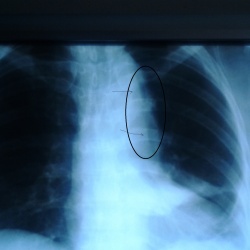

Что это за участки прсветления в ОГК и маммографии. По поводу ОГК больной перенес плеврит недавно, думаю может когда дренаж ставили, средостение повредили и это пневмомедиастинум. По поводу м.ж это...

Какие мнения будут по флюорограмме?